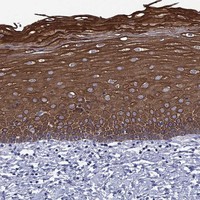

Immunohistochemical staining of human cervix, uterine shows strong cytoplasmic and nuclear membranous positivity in squamous epithelial cells.